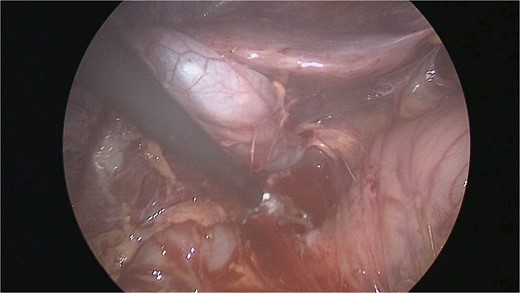

There were extensive perihepatic adhesions with involvement of the subhepatic space (Fig. 3). The initial intraoperative assessment was that this inflammation was secondary to a prior cholecystitis, but subsequent dissection revealed a pristine gallbladder (Fig. 4) with inflammatory adhesions in the pyloro-duodenal region (Fig. 5). All adhesions encasing the duodenum were lysed and the duodenum was kockerized (Fig. 6).

The gallbladder was dissected free of the dense adhesions. There was no evidence of previous cholecystitis. The stomach (short arrow) was spared of adhesions, but the first and second parts of the duodenum were encased (long arrows).